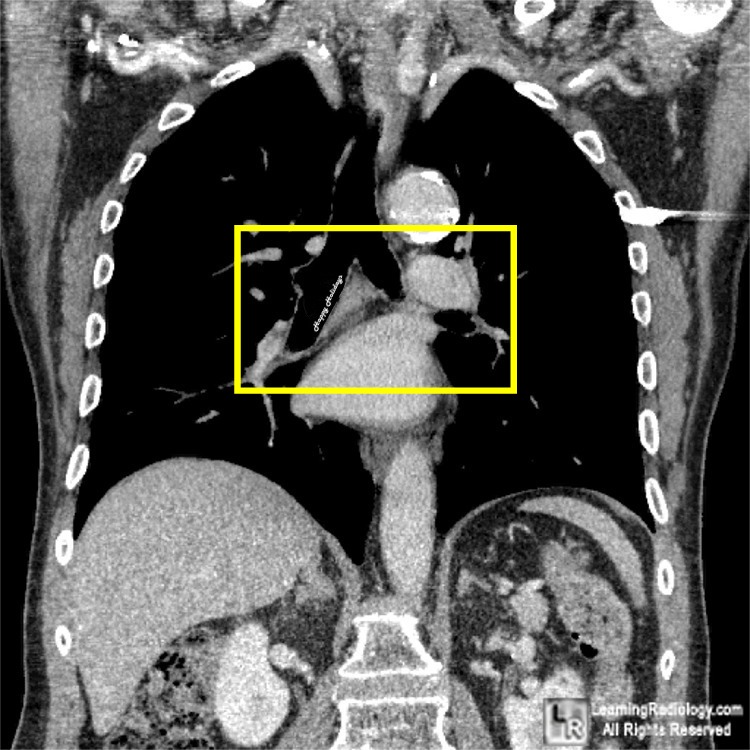

Additional Image - Close-up of right main bronchus

Mouse over for extreme close-up

This is a retouched photograph of a coronal reformatted CT scan of the chest. There is no foreign body present.